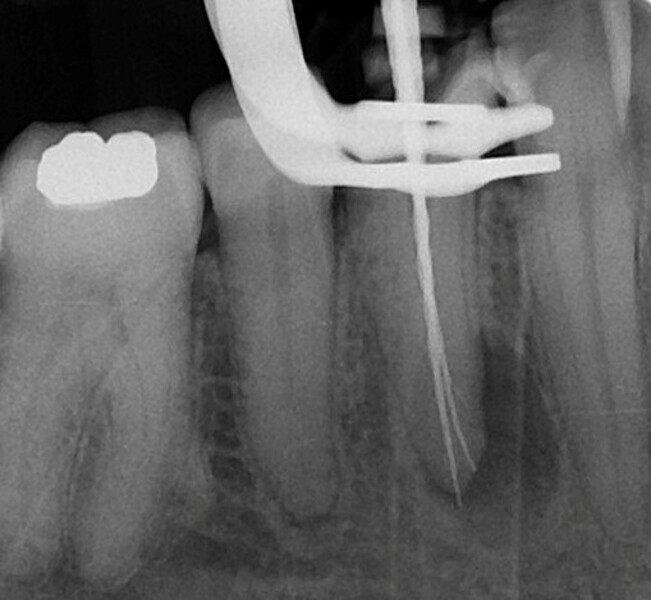

Shaping a Type V mandibular premolar with VDW.ROTATE